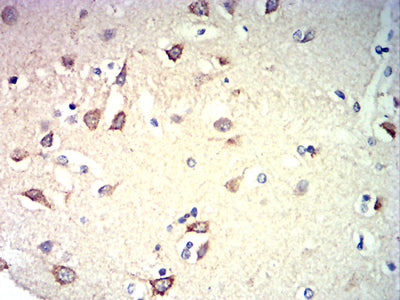

分类: 科研抗体货号: 31967别名: NK1; CD57; HNK1; LEU7; NK-1; GLCATP; GLCUATP应用: IHC,FCM反应种属: Human